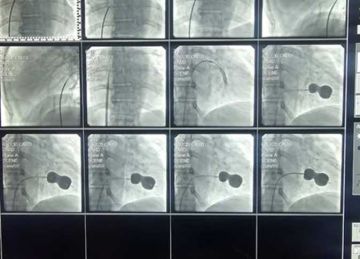

نجاح فريق طبي في جراحة دقيقة لاستبدال الصمام الميترالي لمريضة بالإسكندرية (صور)